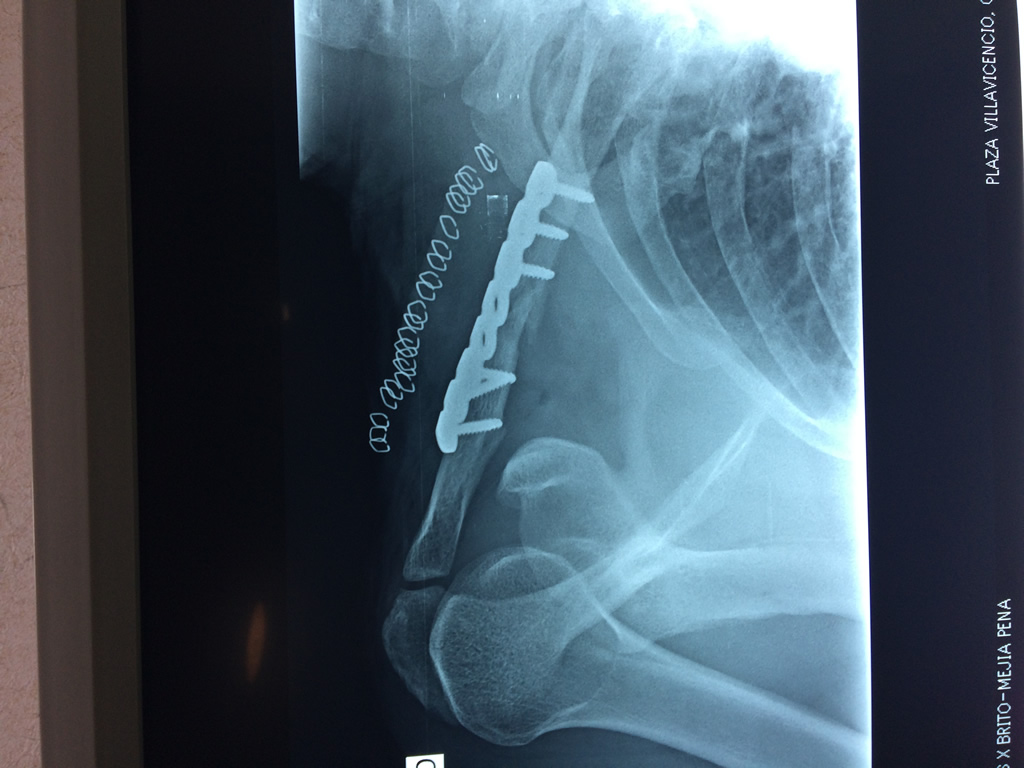

Calcaneo - Clavícula

La clavícula es un hueso largo, con forma de "S" itálica, situado en la parte anterosuperior del tórax. Junto con la escápula forman la cintura escapular. Se puede palpar por toda su longitud y se extiende del esternón al acromion de la escápula, siguiendo una dirección oblicua lateral y posterior.

Se considera el único medio de unión entre el miembro superior y el tórax. A pesar de su aspecto, similar al de un hueso largo, posee una estructura semejante a la de un hueso plano, ya que carece de epífisis y de diáfisis, lo que la harían entrar dentro de la clasificación de hueso largo. Carece de un canal medular propiamente dicho.